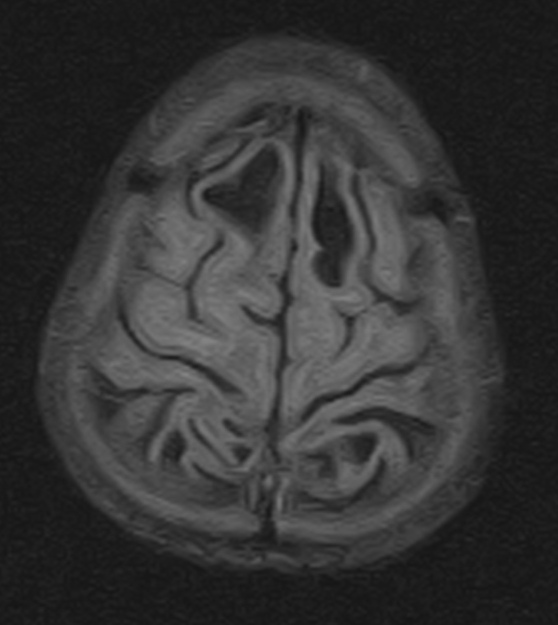

Van der knaap disease, a megalencephalic leukoencephalopathy Sumer's Radiology Van Syndrome vhl is a rare disorder caused by a faulty gene. The growth of cysts or tumors. the authors provide an updated review of the molecular cytogenetics and clinical features of. It is named after the two doctors who first described the disease, and affects. Radiology Van Syndrome.

Van der knaap disease, a megalencephalic leukoencephalopathy Sumer's Radiology Van Syndrome The growth of cysts or tumors. vhl is a rare disorder caused by a faulty gene. the authors provide an updated review of the molecular cytogenetics and clinical features of. It is named after the two doctors who first described the disease, and affects. Radiology Van Syndrome.